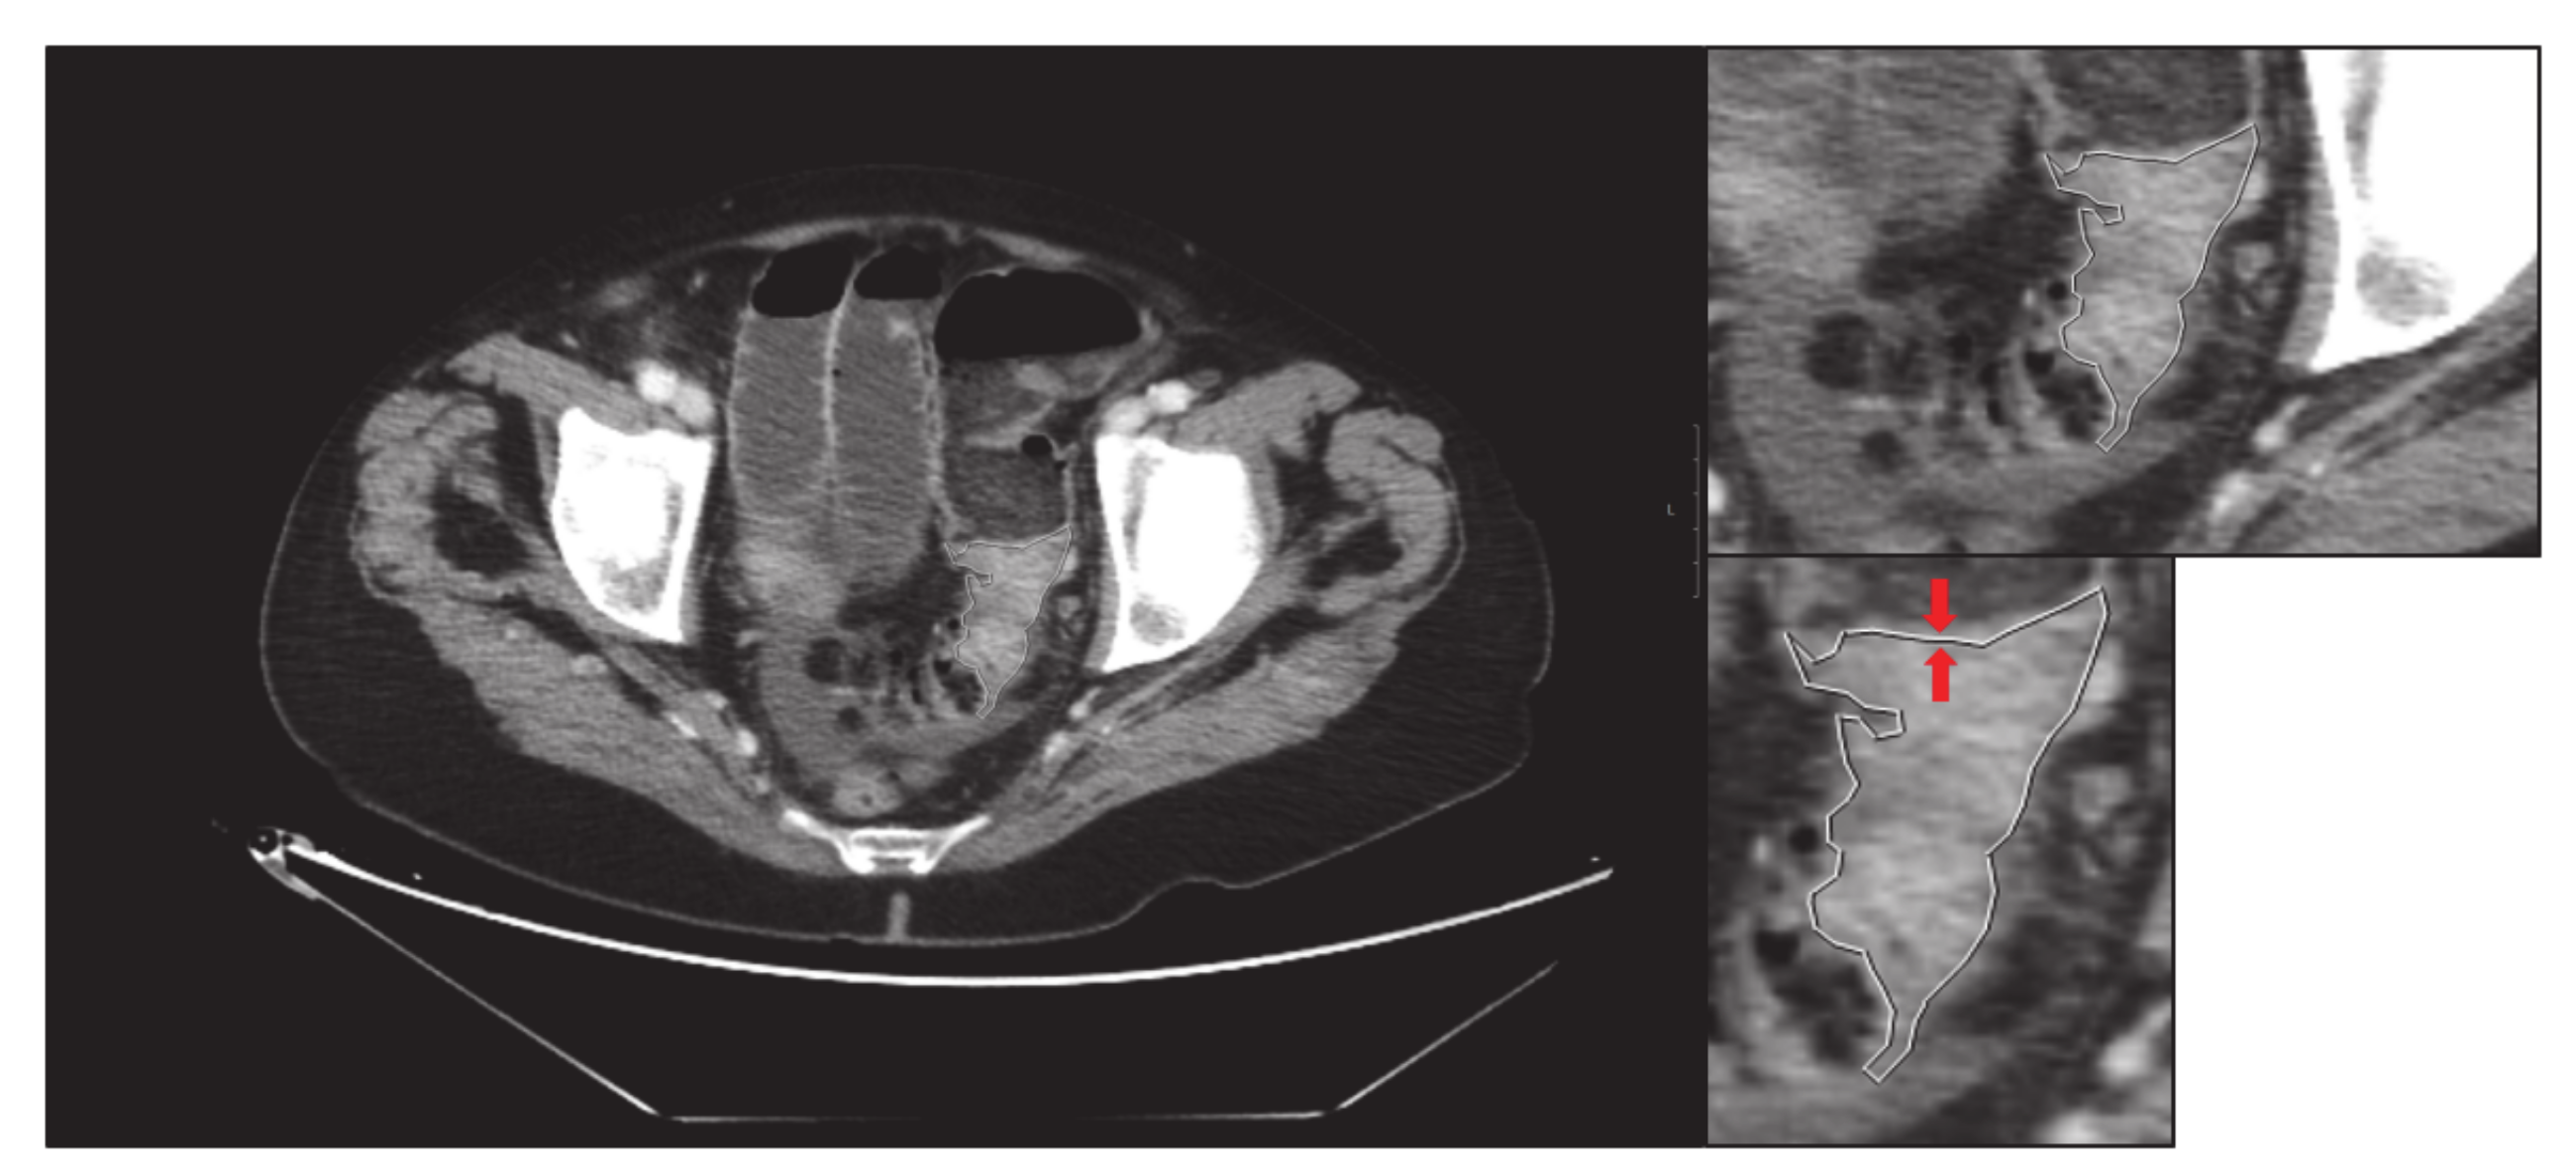

- Third, the screen zoom is adjusted by enlarging the image and an image of the segmented and enlarged tumour is saved: “small-delimited.tiff” (i.e., Figure 3).

- Finally, without modifying the zoom, the previous delimitation is eliminated, and one image of the tumour is saved without delimiting and enlarged: “small-original.tiff” (i.e., Figure 4).